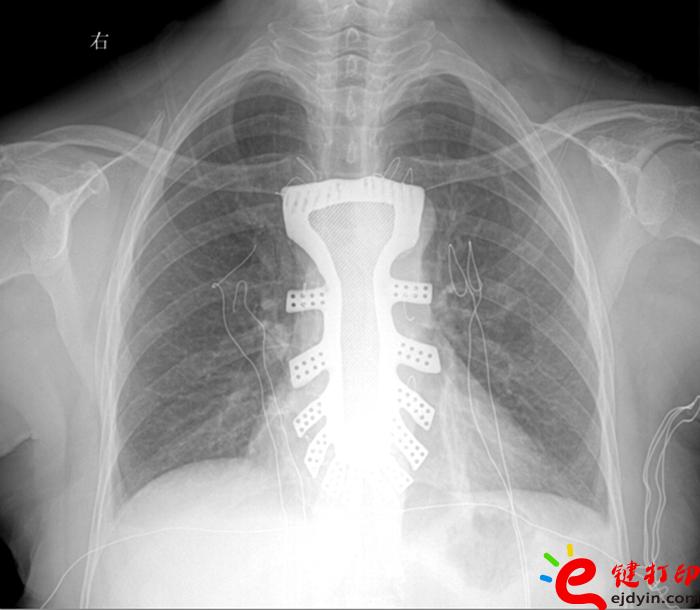

據(jù)王小平教授介紹,唐都醫(yī)院3D打印小組經(jīng)過(guò)精密計(jì)算患者胸骨的大小、形狀等,充分研究討論,歷時(shí)一周,為患者設(shè)計(jì)出了手術(shù)使用的3D胸骨模型,并與西北工業(yè)大學(xué)凝固技術(shù)國(guó)家重點(diǎn)實(shí)驗(yàn)室合作,為患者打印出了1:1鈦合金胸骨模型。隨后,又對(duì)該模型進(jìn)行了一系列嚴(yán)密的醫(yī)學(xué)處理。

“手術(shù)歷時(shí)2.5小時(shí),對(duì)患者的胸骨進(jìn)行了整體切除,置換了鈦合金胸骨,目前患者恢復(fù)良好,未發(fā)現(xiàn)任何并發(fā)癥。”王小平教授稱,根據(jù)專業(yè)機(jī)構(gòu)檢索,該手術(shù)是世界首例針對(duì)胸骨腫瘤疾病,將3D打印的可植入性鈦合金胸骨植入人體,實(shí)現(xiàn)病變胸骨的整體置換的手術(shù)。該手術(shù)的成功意味著未來(lái)將會(huì)為更多的胸骨腫瘤患者帶來(lái)福音。